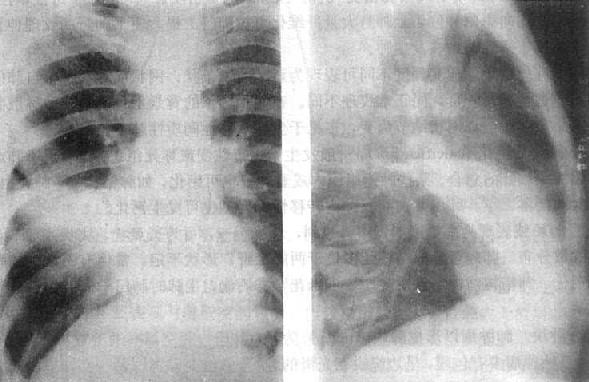

2)右肺中叶不张:较为常见,后前位表现为右肺下野内侧靠心右缘现上界清楚下界模糊的片状致密影,心右缘不能分辨(图3-1-9)。侧位上表现为自肺门向前下方倾斜的带状或尖端指向肺门的三角形致密影(图3-1-9)。上、下叶可有代偿性肺气肿。

图3-1-9 右肺中叶肺不张(正、侧位)